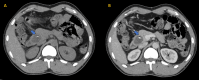

Figure 2

Figure 2. (A) Axial contrast-enhanced CT scan image of the abdomen in portal venous phase at the level of the pancreas shows a well-defined solid cystic mass in the body and tail of the pancreas. (B) Microscopic section of the pancreas shows tumor cells arranged in solid and pseudo-papillary pattern, solid areas comprising monomorphic cells admixed with capillary-sized blood vessels, and pseudo-papillae formed by tumor cells around the blood vessels, getting detached at places (H&E stain, original magnification 20×). It was proven to be a case of SPEN

CT: computed tomography; H&E: hematoxylin and eosin; SPEN: solid pseudo-papillary epithelial neoplasm